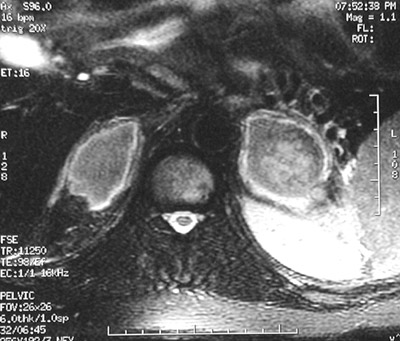

| The abdominal spin echo T1 weighted MRI scan above reveals bilateral adrenal hemorrhages on the right and on the left. In addition to meningococcemia, other etiologies could include coagulopathy, hemorrhagic cortical carcinoma, and adrenal vein thrombosis with infarction. The view below is a fast spin echo T2 weighted MRI scan. |